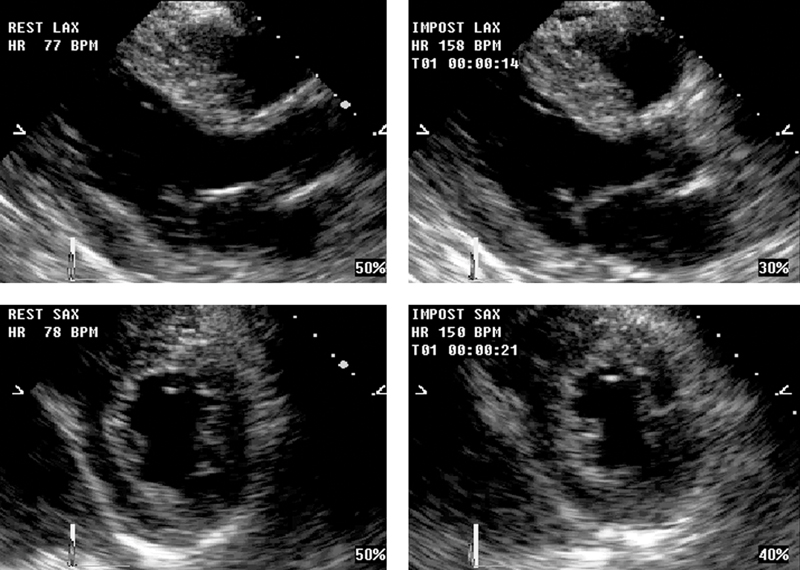

فحوصات تشخيصية لبعض امراض القلب والشرايين التاجية